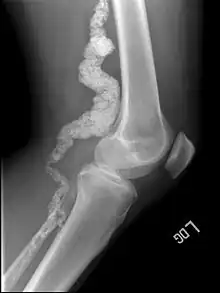

| A knee x-ray of a person with ACDC | |